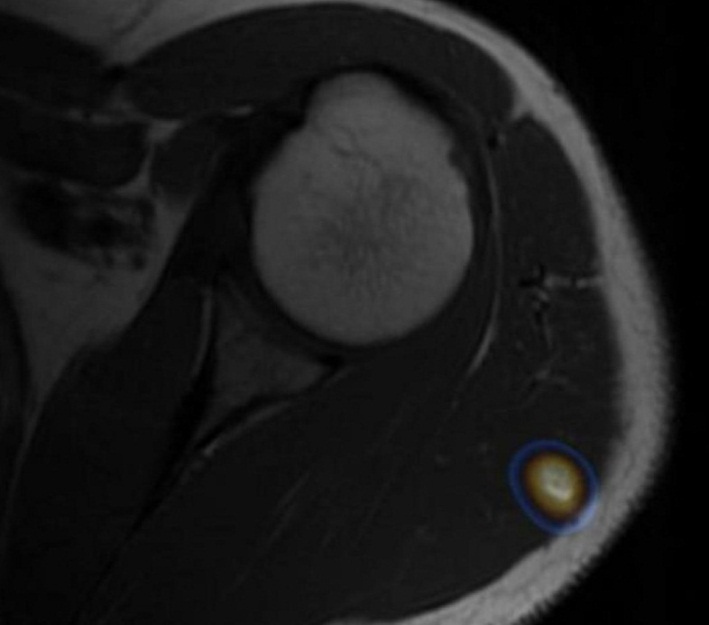

Es llevado a tiroidectomía total con vaciamiento ganglionar central y bilateral de cuello. El reporte anatomopatológico informa carcinoma papilar de tiroides de patrón clásico, multifocal, pT2(m), pN1b, cM1, Estadio II, con alto riesgo de recurrencia. Se indicó terapia con 7400 MBq (200 mCi) de I-131, con estudios bioquímicos que evidenciaron TSH 14,8 uUI/ml, tiroglobulina 500 ng/ml y anticuerpos antitiroglobulina negativos. Se realizó rastreo corporal total de control (Fig. 1), encontrándose dos restos tiroideos además de compromiso metastásico pulmonar y áreas yodocaptantes en húmero proximal y fémur izquierdo, coxofemoral ipsilateral y tibia derecha. Con el objetivo de realizar correlación anátomo-funcional se decidió solicitar resonancia magnética (RM) de hombro izquierdo, pelvis y miembros inferiores (Fig. 2). Se evidencia lesión intramuscular en la porción posterior del músculo deltoides izquierdo y lesión con captación de medio de contraste en músculo sóleo derecho, las cuales son concordantes con los hallazgos descritos en el rastreo corporal total y sugestivas de compromiso metastásico.

Se observó persistencia de captación en campos pulmonares, además de disminución de las lesiones yodocaptantes en región deltoidea izquierda y tibial proximal, con desaparición de la captación en fémur izquierdo (Figs. 4 y 5). Con este resultado, se realizó RM de control de hombro izquierdo y miembros inferiores, visualizándose disminución en el tamaño de las lesiones.